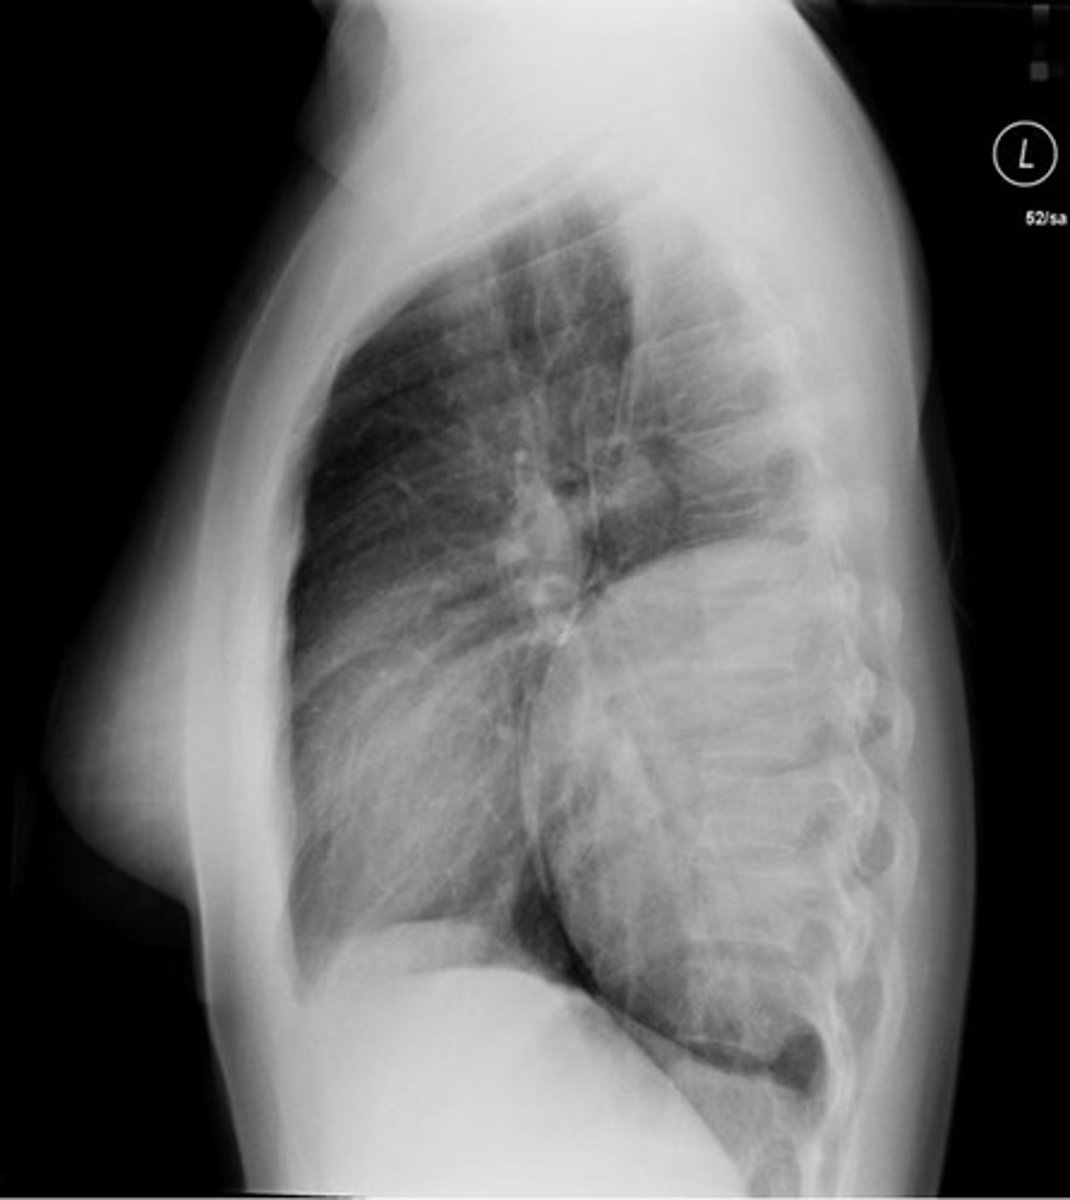

How does COPD appear on an XR

-very small, blister like lesion on visceral pleura normally at apex